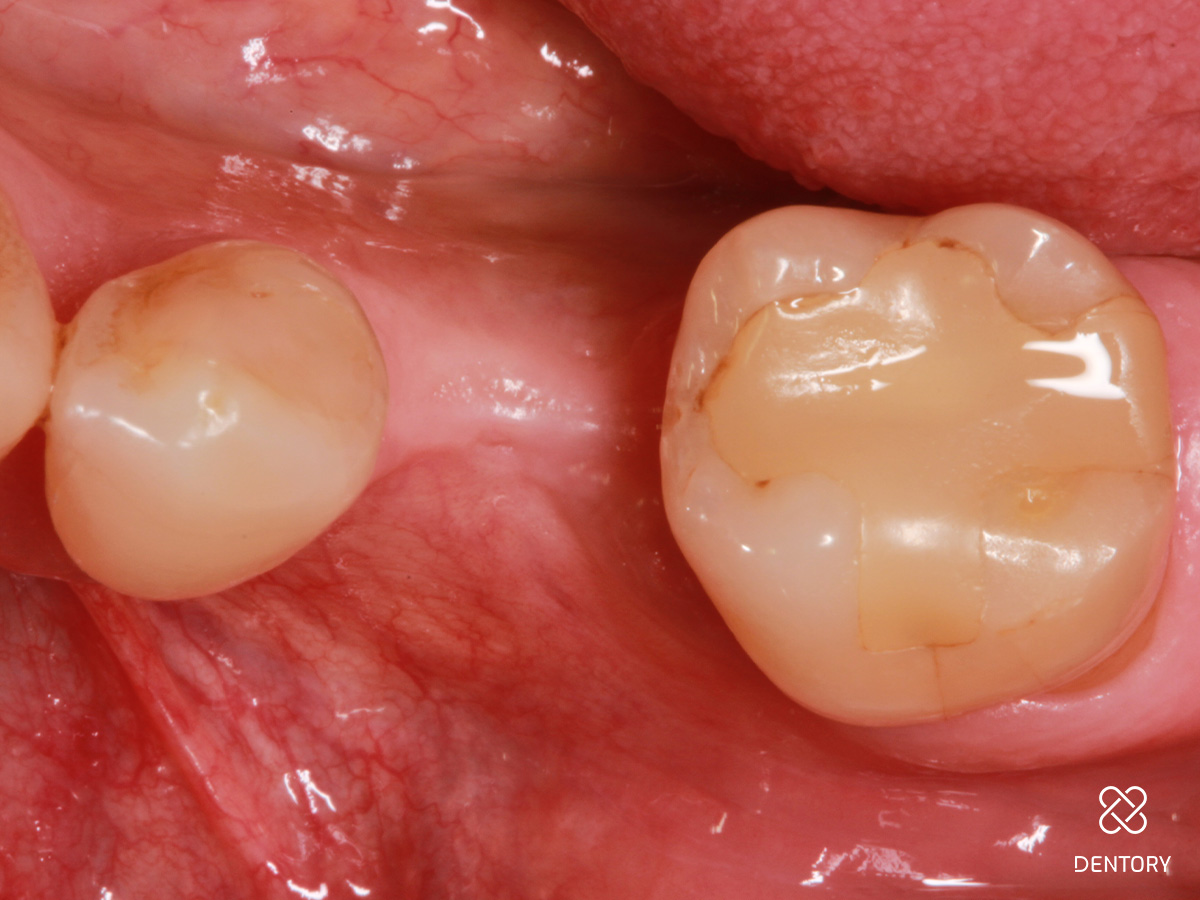

Abbildung 10

Klinische Situation 4 Monaten nach Implantation und GBR: es zeigt sich eine deutliche Volumenzunahme mit Korrektur des Defektes.